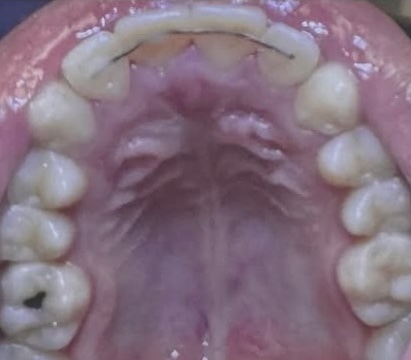

Crowding and constricted arch. Comprehensive orthodontic treatment was performed, and teeth alignment was restored.